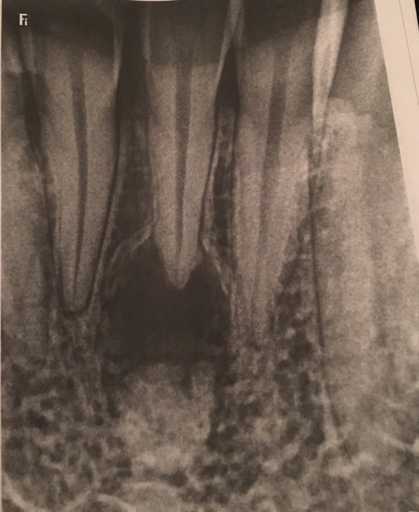

How should I fix the problem with my transmigrated mandibular canine?

I have a transmigrated mandibular canine. It is very far into my jaw. My orthodontist decided to attach a button onto the tooth, run a chain through my gums and attach it to my 2nd furthest back tooth. This constant pressure is moving the tooth into poison. Right now my midlines are so messed up to make room for this tooth to come in. We recently found out that the 2nd furthest back canine (which should be an anchor) is actually moving forward and the transmigrated tooth is acting as an anchor. I had surgery in January of 2018 and they removed some of my jaw to attach the button to my tooth. Now, they want to do surgery again and remove the transmigrated tooth. Then, they want to move forward one of my teeth and shave it down so it looks like a canine so I have a gap in the back instead of the front. What do you recommend?